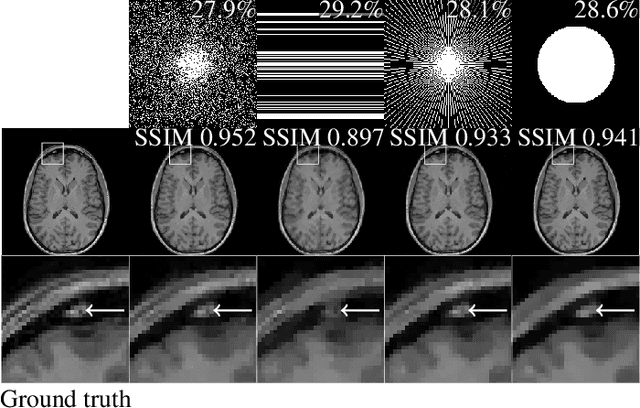

The discovery of the theory of compressed sensing brought the realisation that many inverse problems can be solved even when measurements are "incomplete". This is particularly interesting in magnetic resonance imaging (MRI), where long acquisition times can limit its use. In this work, we consider the problem of learning a sparse sampling pattern that can be used to optimally balance acquisition time versus quality of the reconstructed image. We use a supervised learning approach, making the assumption that our training data is representative enough of new data acquisitions. We demonstrate that this is indeed the case, even if the training data consists of just 5 training pairs of measurements and ground-truth images; with a training set of brain images of size 192 by 192, for instance, one of the learned patterns samples only 32% of k-space, however results in reconstructions with mean SSIM 0.956 on a test set of similar images. The proposed framework is general enough to learn arbitrary sampling patterns, including common patterns such as Cartesian, spiral and radial sampling.